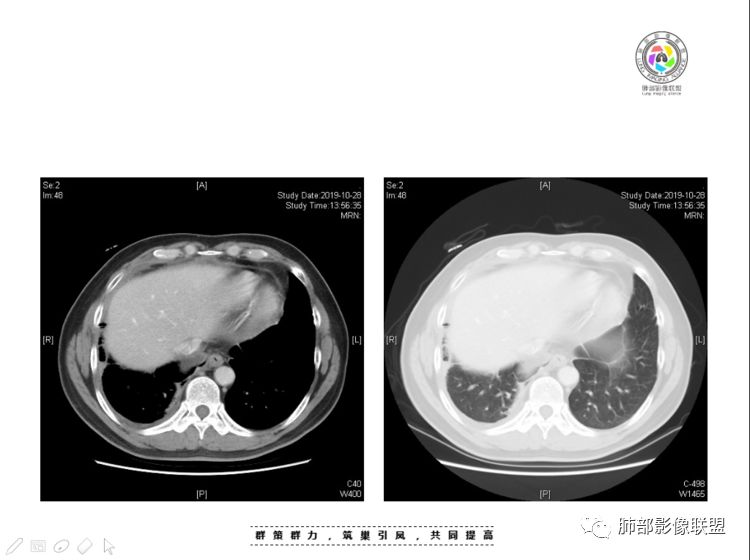

肺内结节,近端支气管堵塞狭窄

整体边缘收缩,部分膨隆

炎性要考虑,但恶性不能排除

1、右肺内病灶,病灶呈结节样,边缘欠规则,局部膨隆,叶间裂胸膜牵拉凹陷,再看相应支气管腔堵塞截断,临床资料胸水中查到癌细胞,均提示病灶倾向恶性,腺癌的病理意见与之相吻合。

黄勇老师总结,腺癌如果与胸膜、叶间裂紧贴或伴胸膜凹陷,胸膜、叶间裂多发结节,应当高度怀疑腺癌转移。